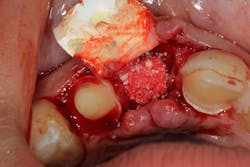

These alveolar bone changes often compromise implant placement due to thin bone volume (figures 2a–2d).

Reduction in quantity and quality of bone can also compromise functional and esthetic outcomes of both implants and fixed bridge restorations (figures 3 and 3a).

• Site development to increase hard and soft tissue for pontic sites in fixed bridge prosthetics (figures 4–4e)

• Rebuild defects around adjacent teeth after extracting teeth due to periodontal disease (figures 5a–5c)